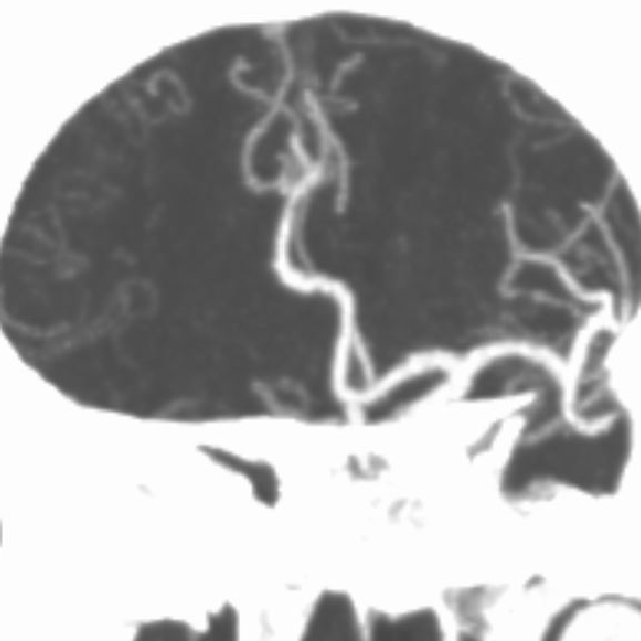

术前CTA:

CTA提示右侧大脑中动脉闭塞,左侧A1纤细。